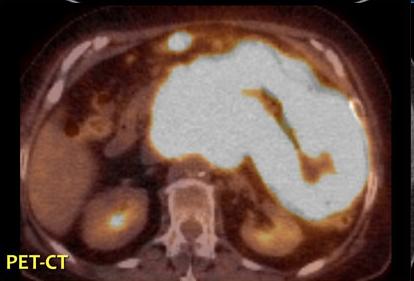

Meme cas en PET /CT . Coupe

axiale . |

| |